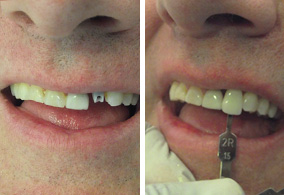

Es un procedimiento que permite recuperar las piezas faltantes en una sola sesión en la que se colocan los implantes dentales y se rehabilitan con sus prótesis, son muy pocos los casos en los que este procedimiento está indicado, una vez recibido este tratamiento es muy importante su cuidado post operatorio.

En Dental Evolution en Cancún, nuestros especialistas evaluarán su caso particular mediante la toma de registros fotográficos, impresiones, historia clínica, tomografía en tercera dimensión que nos permitirán el estudio de la estructura craneofacial y su relación maxilomandibular, calidad y cantidad de hueso con el objeto de determinar su salud bucal, ya que, para recibir un Implante Dental es muy importante tener encías sanas y hueso adecuado que soporte el Implante Dental.